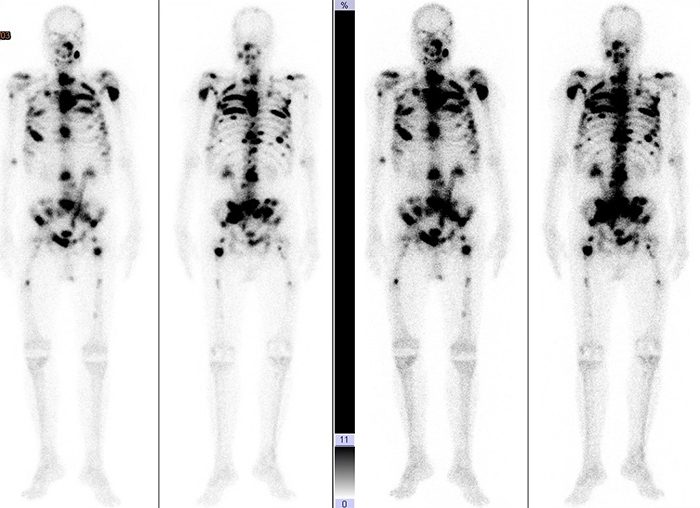

圖一:高風險轉移性攝護腺癌示意圖:骨骼掃描顯示有多發性骨骼轉移。

圖二:實際個案: 林先生(69 y/o),格里森分數5+4=9分、骨骼多處轉移攝護腺癌,經三合一治療,疾病控制良好,PSA從超過1000

ng/ml下降到 0.24 ng/mL。